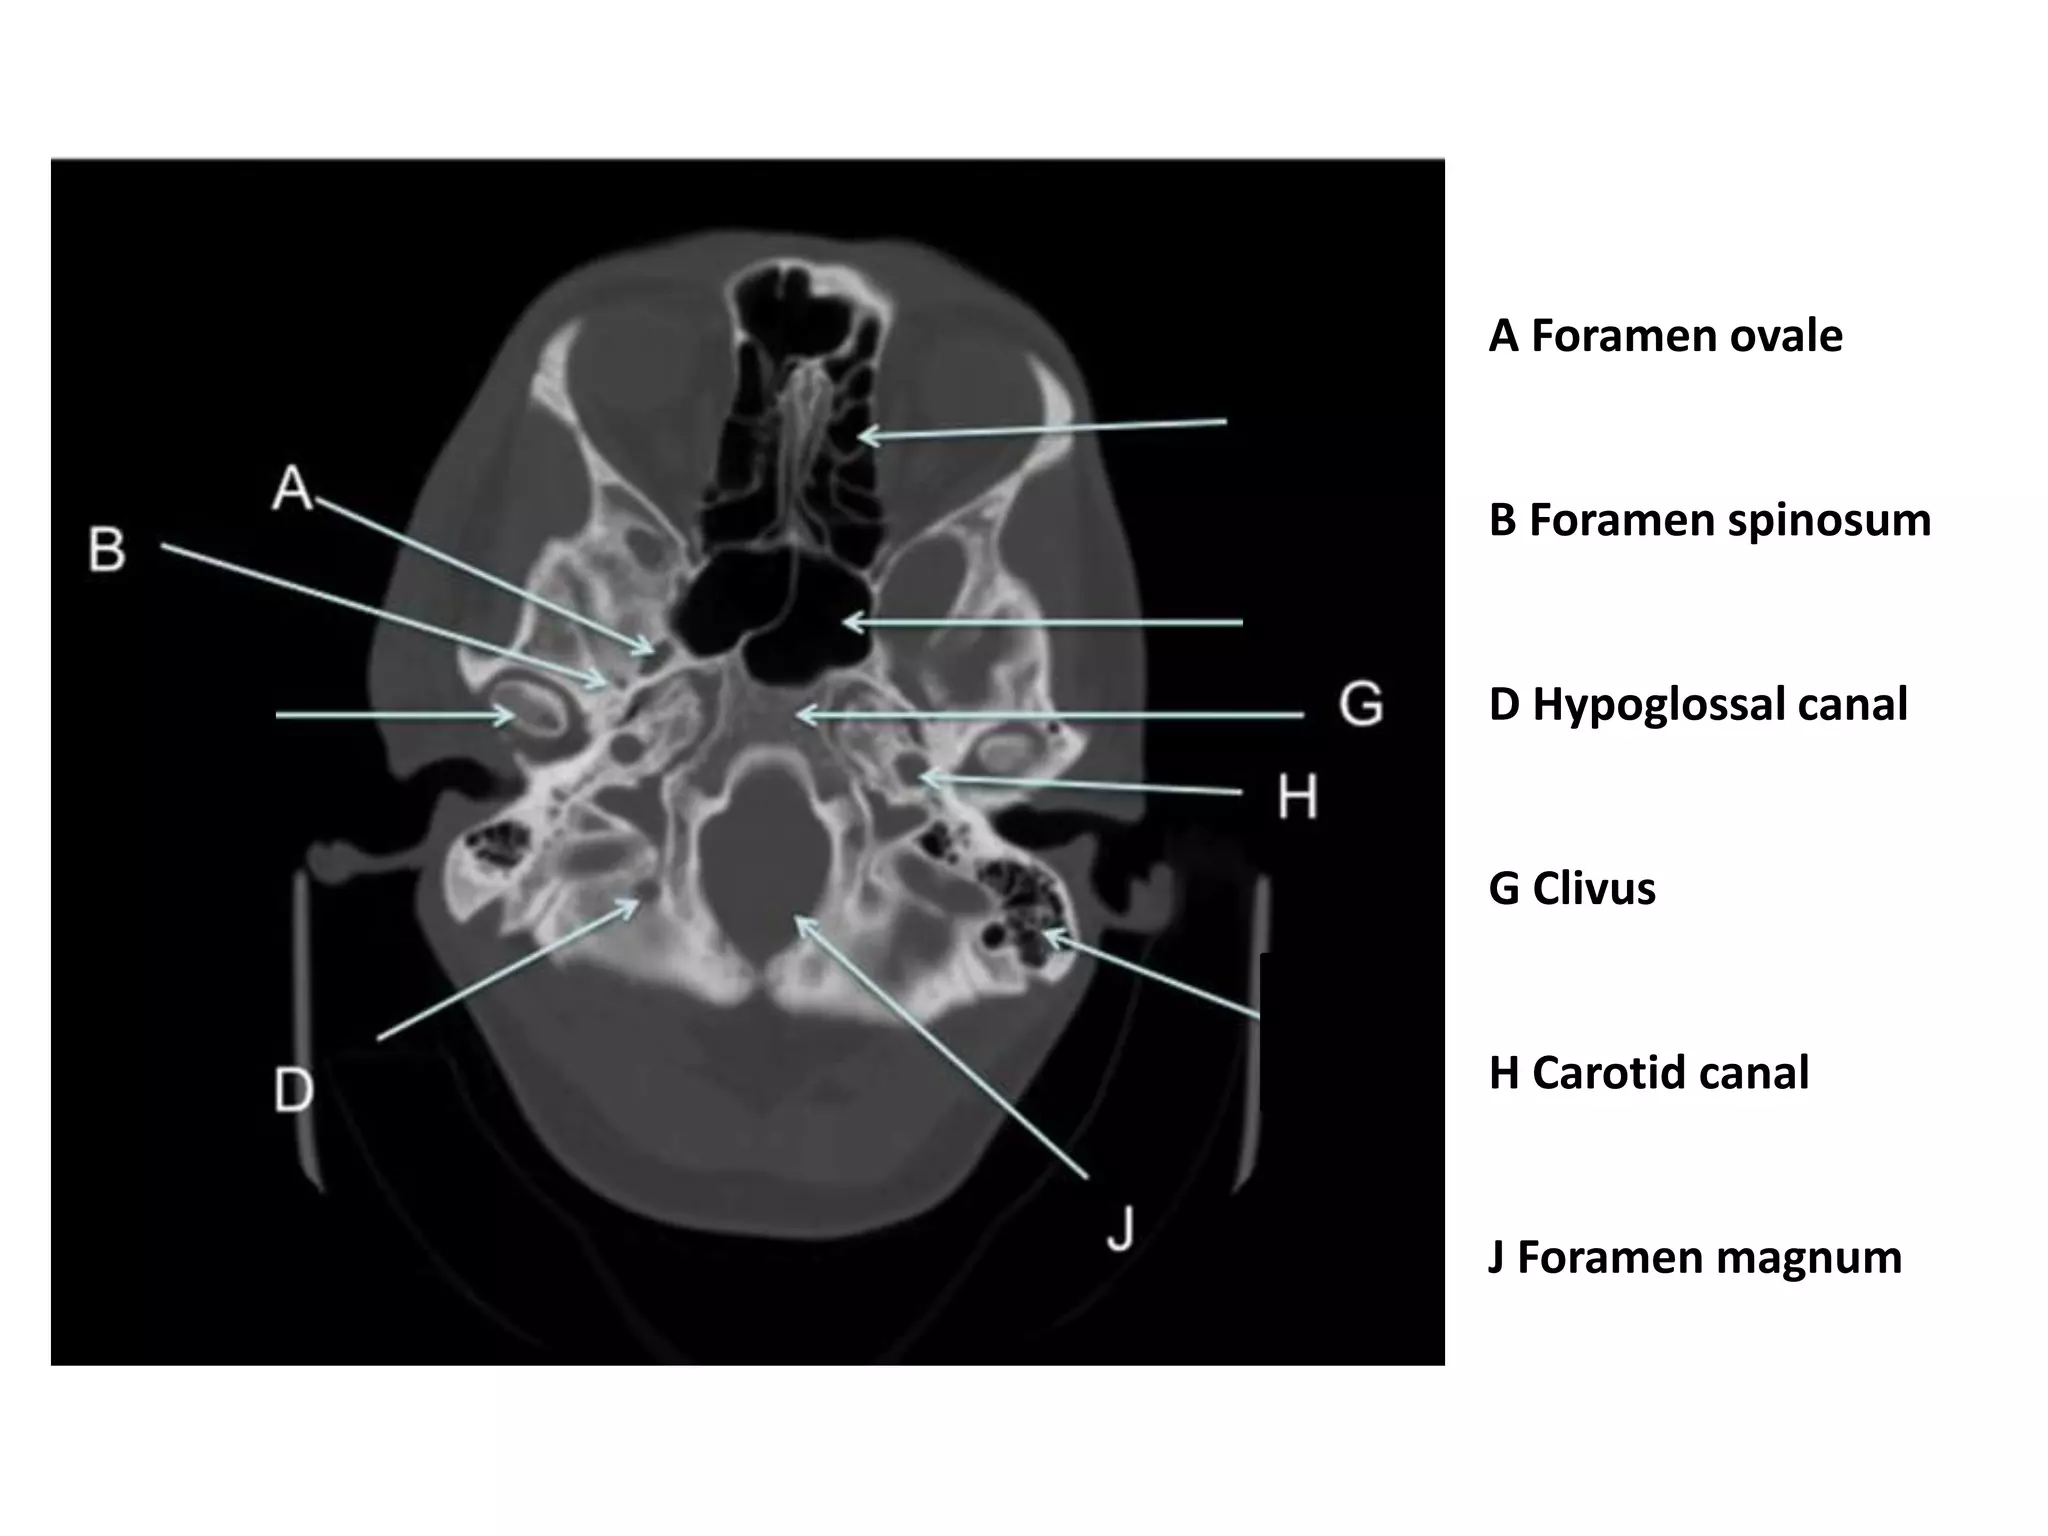

A Foramen ovale

B Foramen spinosum

D Hypoglossal canal

G Clivus

H Carotid canal

J Foramen magnum

FORAMINA • Jugular foramen • F. ovale (4) • F. rotundum • F. spinosum • Carotid canal (5) • F. magnum (7) • F. lacerum (9) • Hypoglossal canal (11) 11

A Foramen ovale BForamen spinosum D Hypoglossal canal G Clivus H Carotid canal J Foramen magnum